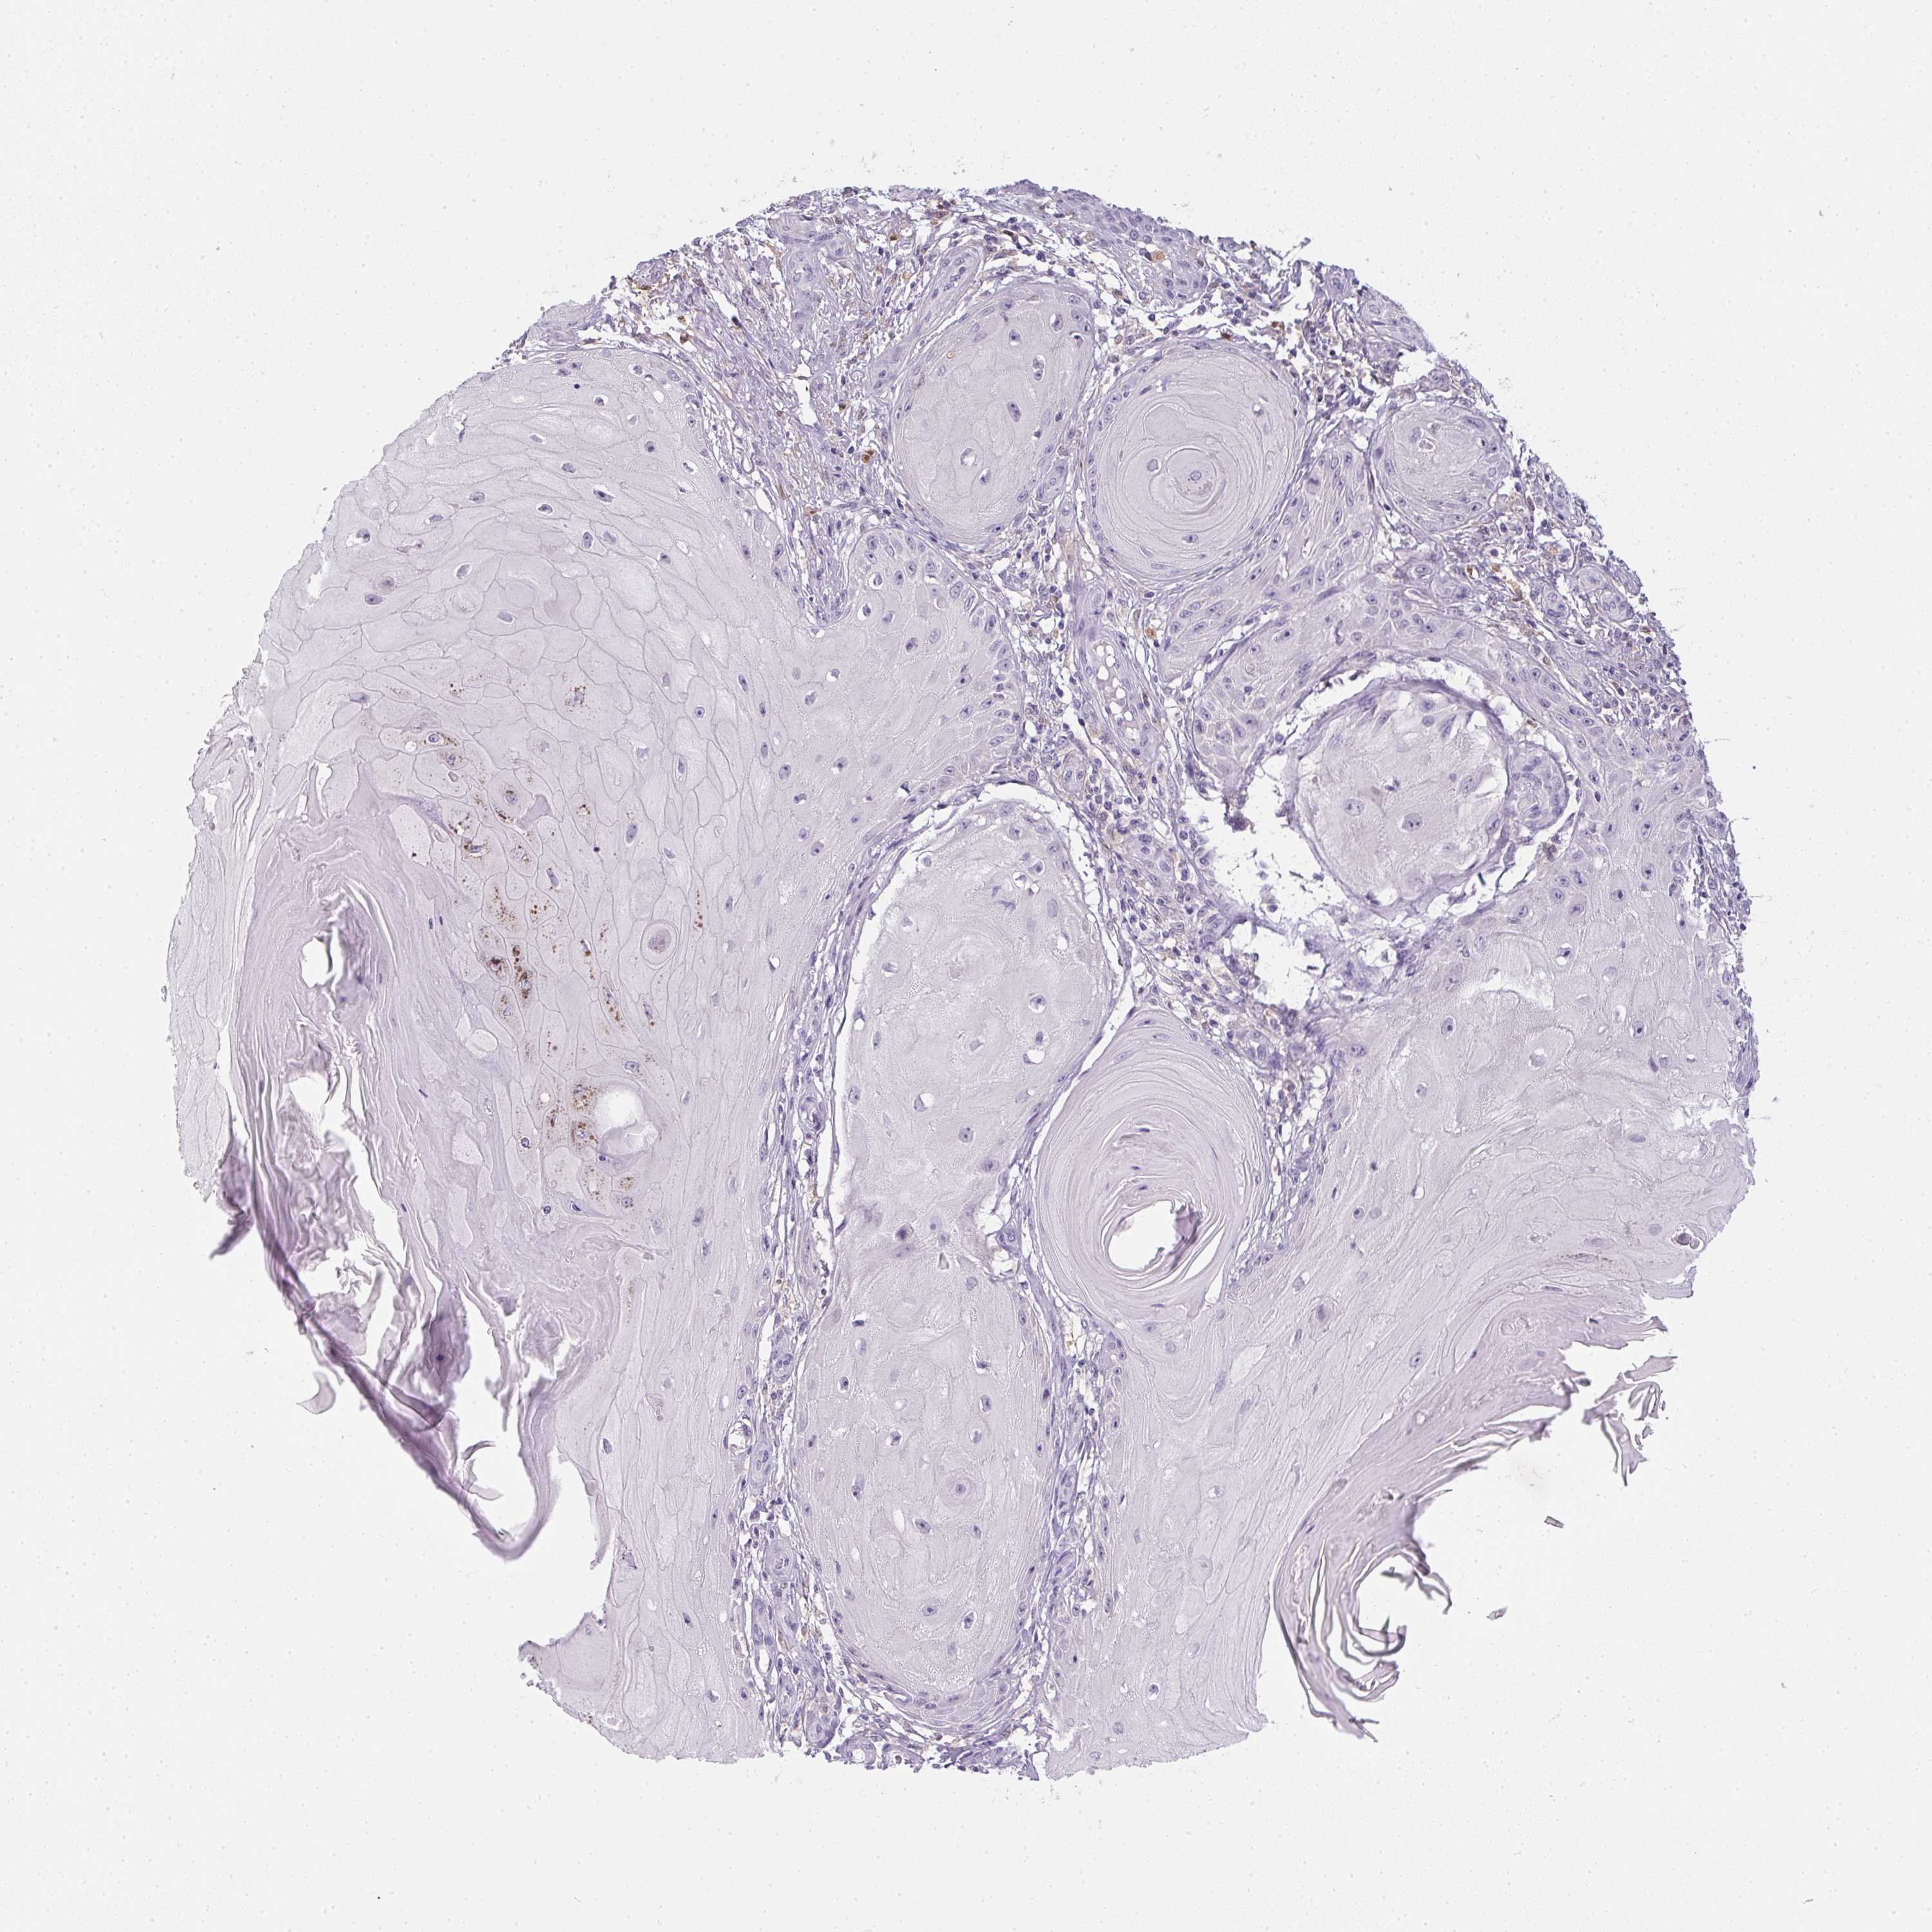

Basal cell and squamous cell cancer

SKIN CANCER - Protein expressioni

A mouse-over function shows sample information and annotation data. Click on an image to view it in a full screen mode. Samples can be filtered based on level of antibody staining by selecting one or several of the following categories: high, medium, low and not detected. The assay and annotation is described here.

Antibody stainingi

Antibody staining in the annotated cell types in the current human tissue is reported as not detected, low, medium, or high, based on conventional immunohistochemistry profiling in selected tissues. This score is based on the combination of the staining intensity and fraction of stained cells.

Each image is clickable and will lead to virtual microscopy that enables deeper exploration of all samples and also displays staining intensity scores, fraction scores and subcellular localization as well as patient and tissue information for each sample.

Antibody HPA041445

Staining

High

Medium

Low

Not detected

Intensity

Strong

Moderate

Weak

Negative

Quantity

>75%

75%-25%

<25%

None

Location

Nuclear

Cytoplasmic/membranous

Cytoplasmic/membranous,nuclear

Basal cell carcinoma

Squamous cell carcinoma, NOS